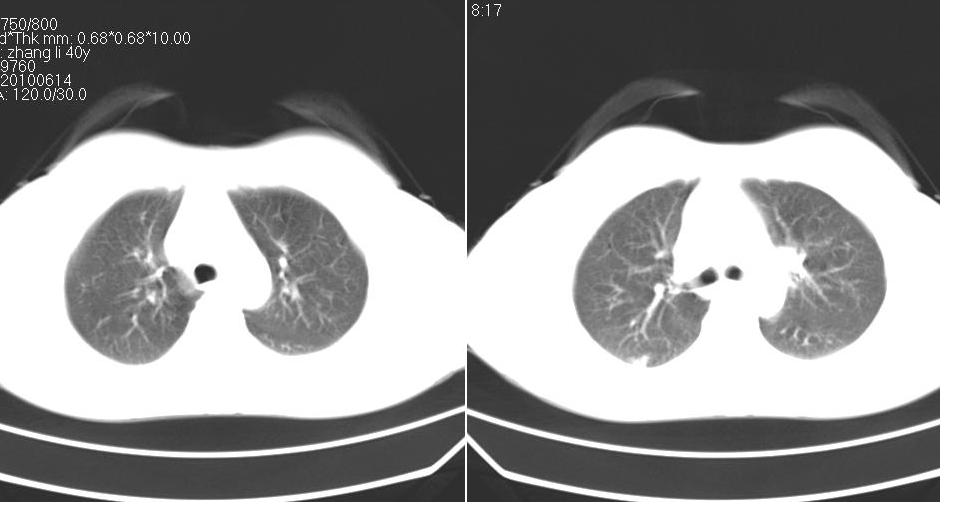

女 40岁,胸片体检发现右肺肿块,无任何症状。

下叶背段多发性小腺泡结节,考虑结核。

考虑右肺下叶背段继发性肺结核。

考虑右肺下叶继发性肺结核!